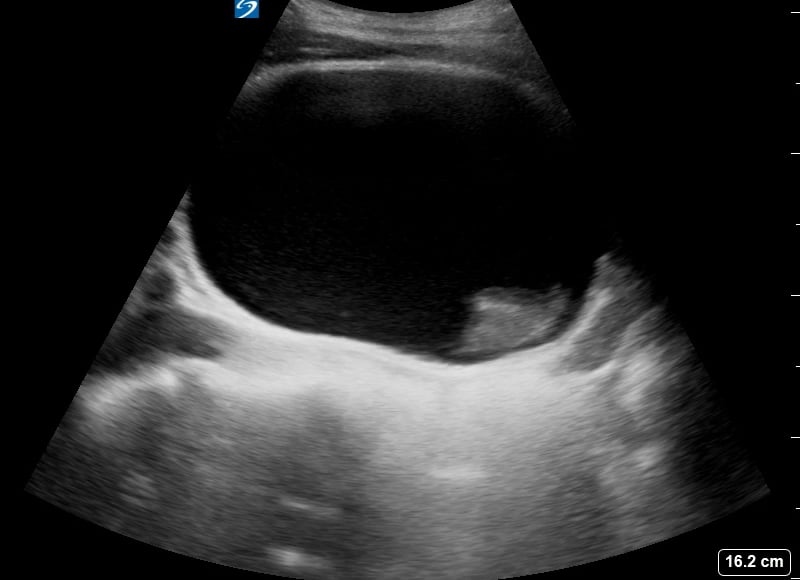

A hematoma, in musculoskeletal (MSK) ultrasound, is a localized collection of blood outside of blood vessels, often resulting from trauma, surgery, or underlying conditions. Appearing as a fluid collection on ultrasound, its characteristics vary based on age—from anechoic (fresh) to hyperechoic/heterogeneous (clotted/organizing). MSK ultrasound is crucial for diagnosing, characterizing, and monitoring hematomas, differentiating them from other masses, and guiding interventions.

Accurate ultrasound assessment of MSK hematomas helps clinicians determine size, location, and potential complications like nerve compression or infection. Early identification through medical ultrasound facilitates timely management, improves patient outcomes, and prevents chronic issues, making precise imaging vital for musculoskeletal care.